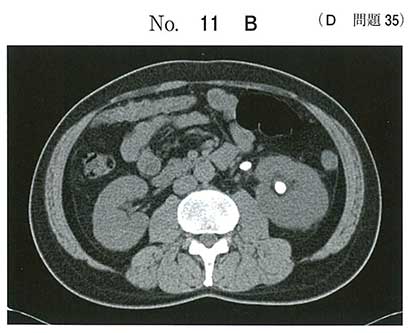

難しいけどx線透過性が低いと考えa

尿酸高いし、レントゲンでうつらないから単純にa

x線陰性結石なので尿酸ですね

尿路結石で一番多いのはシュウ酸カルシウムです

リン酸アンモニウムマグネシウムは感染結石でサンゴ状結石に多いです